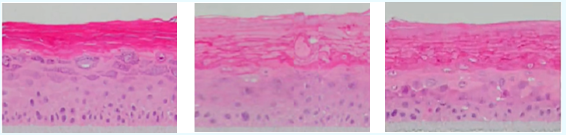

空白對(duì)照組 SLS刺激組 SLS刺激+產(chǎn)品組

由圖可知,當(dāng)皮膚模型受到刺激后,角質(zhì)層分布疏松,下層活細(xì)胞層數(shù)減少,而使用樣品后明顯改善,說明該產(chǎn)品具有良好的舒緩效果。